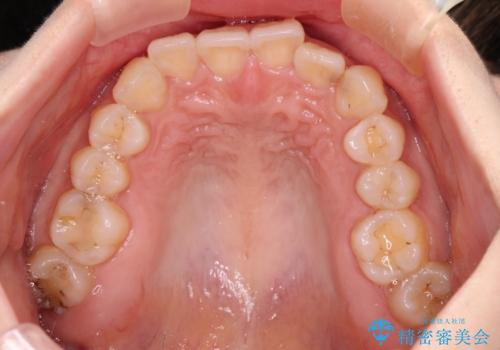

- 前歯のデコボコと深い咬み込みを気にして来院された患者様です。

インビザラインを用いて、前歯の叢生を解消するとともに、深い咬み合わせ(ディープバイト)を改善していくこととしました。

奥歯を後方に直立させることで深い咬み合わせを改善を図り、隠れていた下顎前歯が見えるほどになりました。